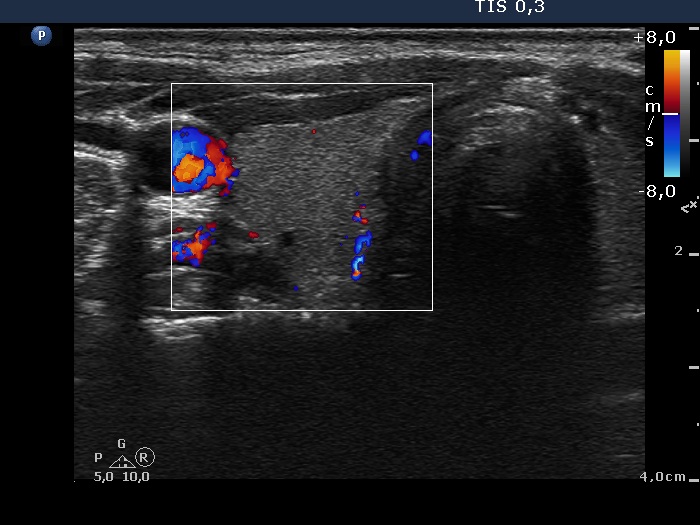

Follow-up examination 3 months later (2nd row of images):

Clinical presentation: The complaints of the patient ceased.

Palpation: The thyroid was not tender, both lobes were firm.

Functional state: hypothyroidism with TSH 2.98 mIU/L and FT4 7.56 pM/L. CRP 1.9 mg/L.

Ultrasonography: The proportion of hypoechogenic areas has decreased. The vascularization became normal.